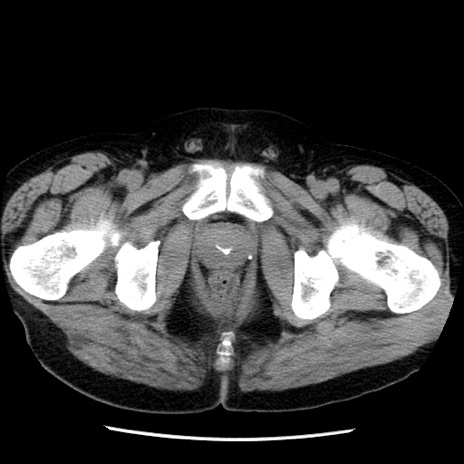

冠状断像

【症例】40歳代男性

【現病歴】2日前から胃痛あり。徐々に周期的な激痛に変化した。本日になっても激痛があるため受診。

【身体所見】意識清明、BT 38-39℃台あり、腹部:膨満、やや硬、右下腹部に圧痛あり。

【データ】WBC 8500、CRP 23.26